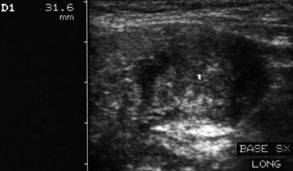

Femeie de 73 ani. Formatiune nodulara mare la baza

lobului stang, de 22 x 34 x 32mm (12 cc), cu contur difuz.

Examen citologic prin citoaspiratie: carcinom papilar confirmat histologic.

Acelasi caz - vascularizatie periferica si intranodulare

bogata.